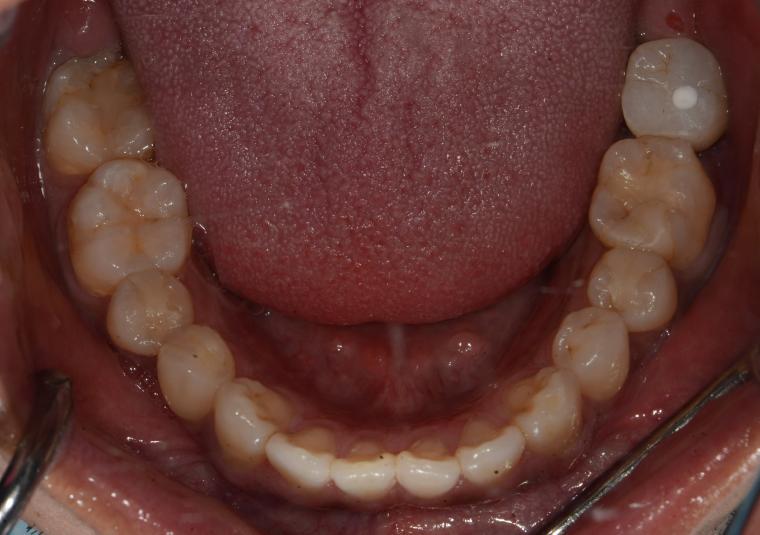

BEFORE

31歳男性/下1本欠損/インプラント埋込手術

左下第二大臼歯が、残根の状態でご来院された患者さんです。

抜歯後に土台となる骨をつくる処置の後、インプラントを埋入しました。